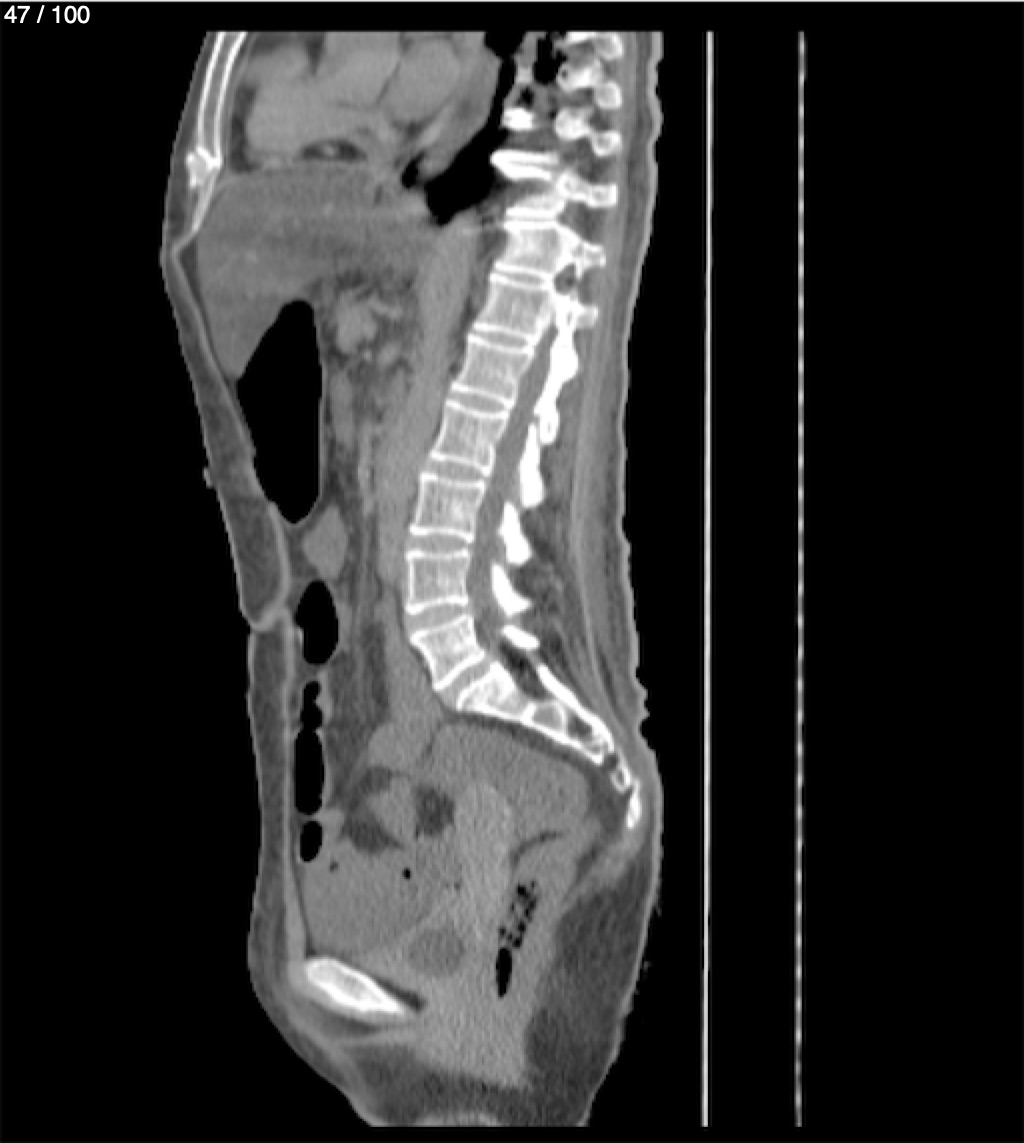

Hilda Geronimo Mendez 60A - T.C Abdomen Simple